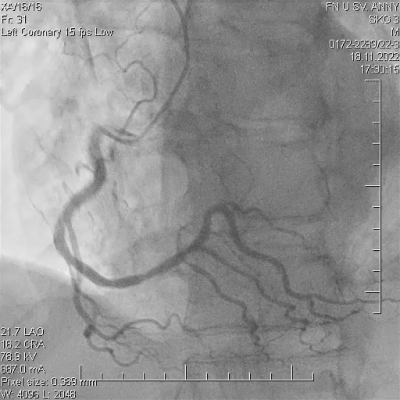

Pacient ve věku 45 let byl referován do našeho kardiocentra po mimonemocniční zástavě oběhu v terénu. Iniciálním nálezem na elektrokardiogramu (EKG)na místě zásahu byla fibrilace komor, byla poskytnuta rozšířená neodkladná resuscitace včetně orotracheální intubace a srdeční defibrilace s obnovením spontánní cirkulace do dvanácti minut. Emergentní selektivní koronarografie neprokázala žádnou významnou stenózu koronárních tepen (video 1, 2, 3), při ventrikulografii byla patrná globální hypokontraktilita levé komory, akcentovaná v oblasti spodní stěny srdeční s celkovou ejekční frakcí levé komory 30 %. V laboratorním nálezu byla s odstupem zjištěna elevace troponinu T stanoveného vysoce senzitivní metodou (hsTnT) – 3 500 ng/l (referenční rozmezí 14 ng/l) a elevovaný C-reaktivní protein (CRP) – 9,3 mg/l (referenční rozmezí 5 mg/l). Anamnéza pacienta zahrnuje bronchiální astma a nosní polypy s medikamentózní terapiísalmeterol/fluticason a omeprazol. Pacient je nekuřák, bez anamnézy abúzu drog.

Na základě těchto výsledků pacient podstoupil opakovanou koronární angiografii, kde byl oproti prvotnímu nálezu pozorován fokální spasmus na ramusinterventricularisanterior (RIA), s jeho úplným odezněním po intrakoronární aplikaci nitrátů (video 4, 5).

V následujících hodinách po výkonu dochází k rozvoji silných bolestí na hrudi jen s částečným odezněním po sublingválním podání nitrátů, na EKG jsou přítomny deprese úseku ST s následnými elevacemi úseku ST ve spodních svodech. Bolesti neustupují ani přes kontinuální intravenózní podávání nitrátů, pacient byl odeslán k provedení emergentní rekoronarografie (celkem třetí v pořadí) s nálezem mnohočetných kritických fokálních spasmů omezujících průtok ve více koronárních povodích (video 6, 7), s jejich postupným úplným odezněním po intrakoronární aplikaci nitrátů a diazepamu (video 8, 9).